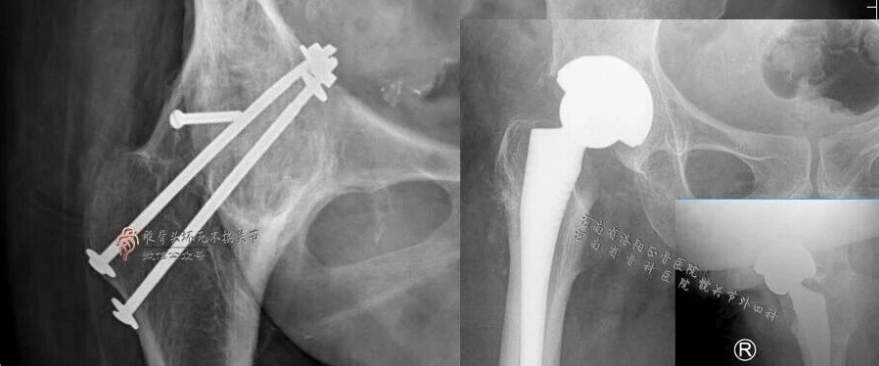

病例一:

病例二: